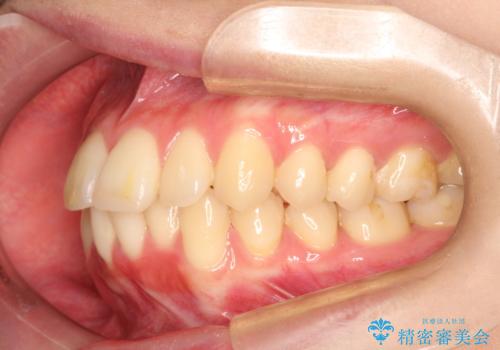

口元が出てるの気になる ハーフリンガルによる抜歯矯正での横顔改善

抜歯矯正により、前歯をしっかり下げることで口元がすっきりしました。